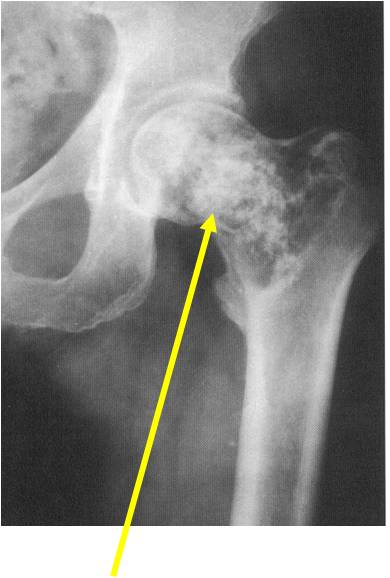

- Epiphyses of long bones

- Most commonly proximal femur, proximal humerus, distal femur, proximal tibia

- Usually osteolytic, expansile lesion

- May be focally calcified

- Often a sharp interface between tumor and surrounding bone

- Overlying cortex is usually thin, but intact